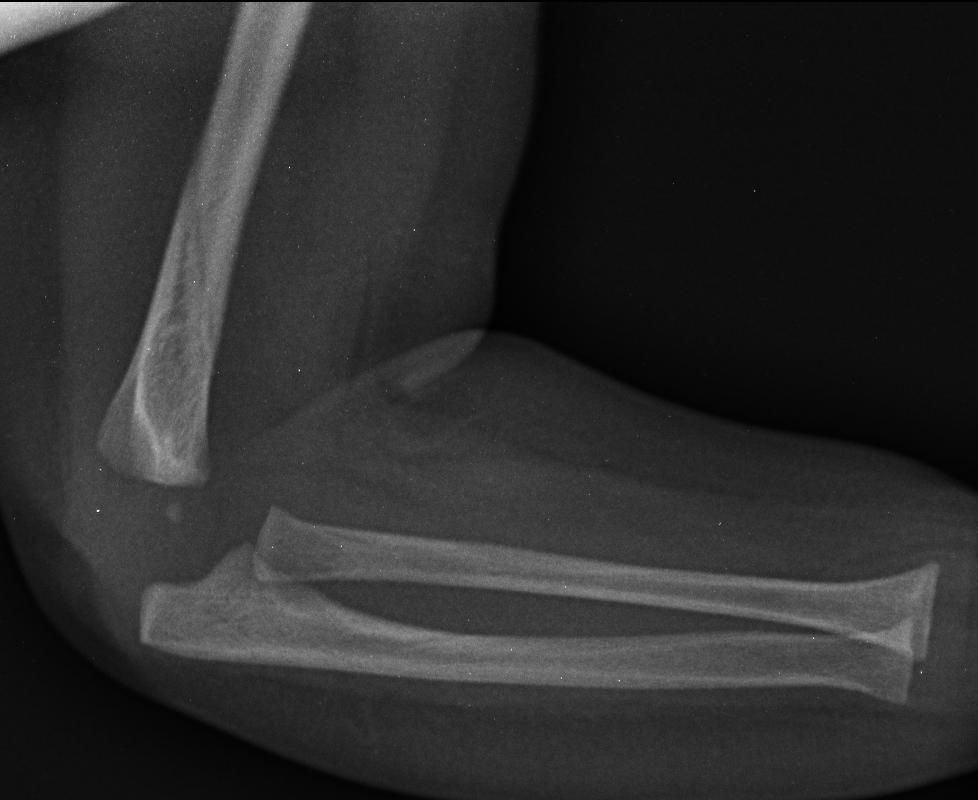

You are seeing 5 month old Carly, who has presented to ED with her parents with an arm injury. Please take a history from her mother.

Case courtesy of Maulik S Patel, Radiopaedia.org, rID: 55891